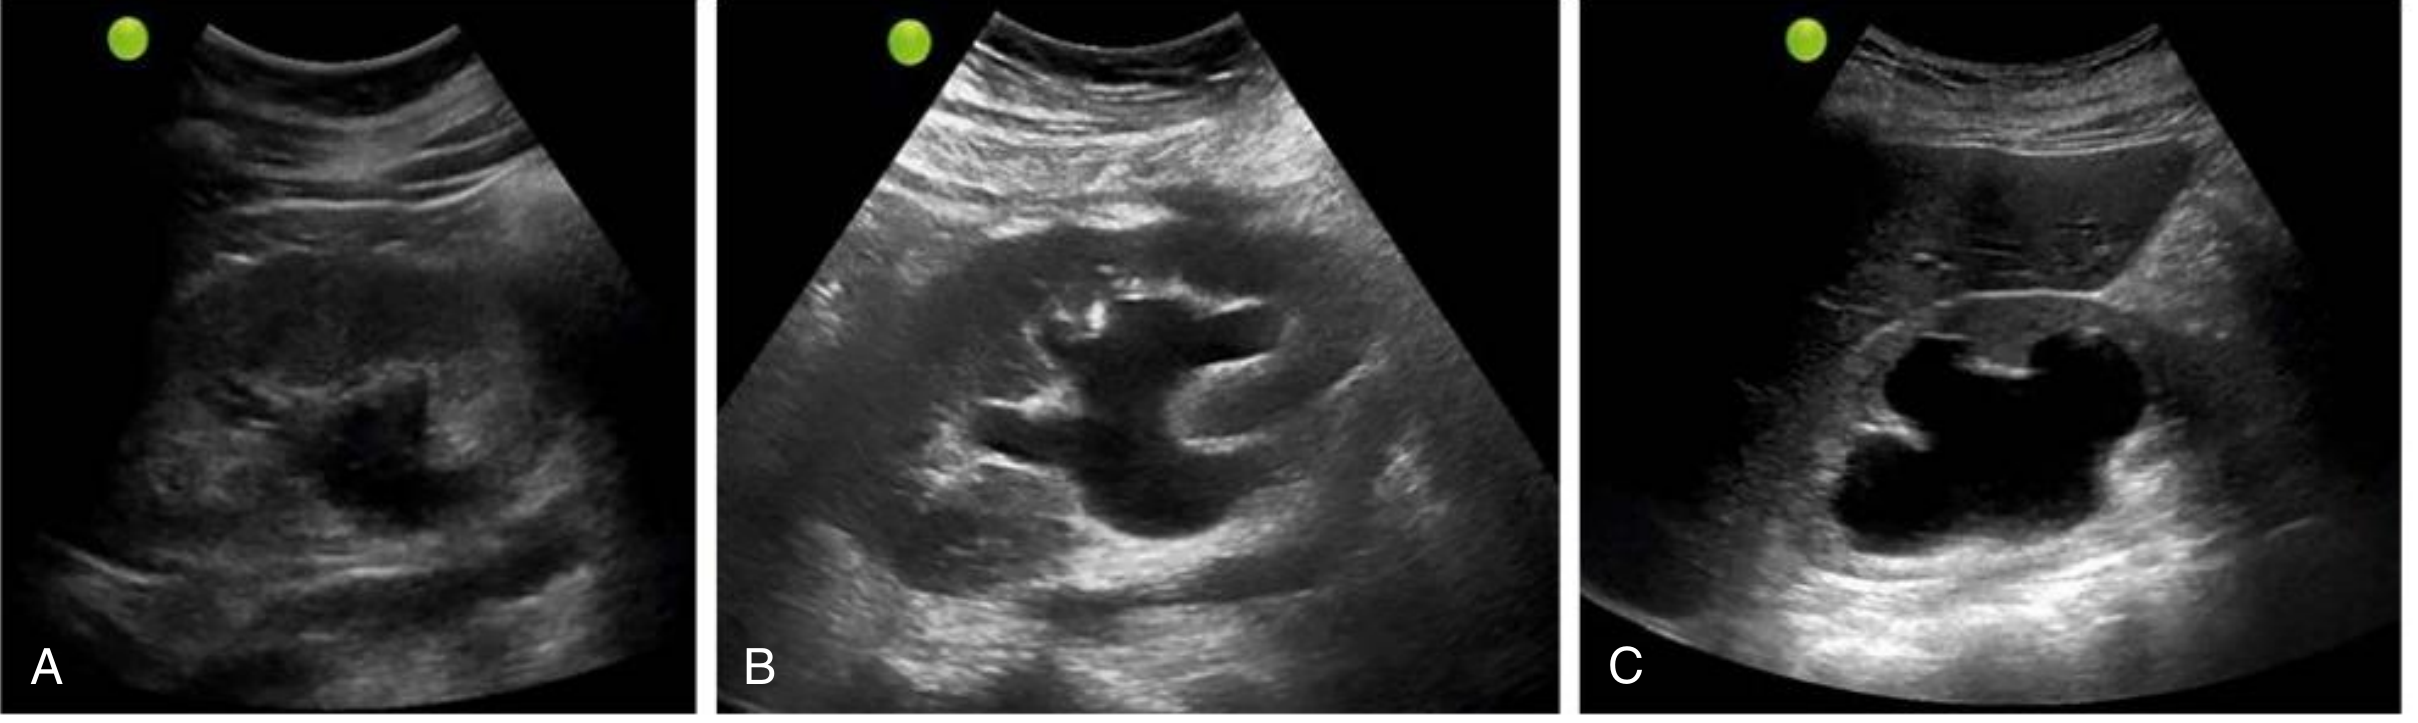

• Mild: dilation of renal pelvis and calyces; parenchymal architecture preserved

• Moderate: medullary pyramids begin to flatten; increasing pelvicalyceal dilation

• Severe: ballooned renal pelvis and calyces (occupying most of kidney); corticomedullary differentiation lost; parenchyma thin

Ultrasound showing mild (A), moderate (B), and severe (C) hydronephrosis

Fig: Mild, moderate, and severe hydronephrosis on ultrasound (Comprehensive Clinical Nephrology)